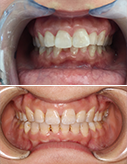

去除牙齿贴面